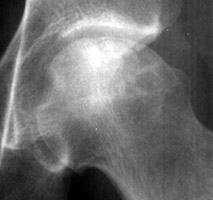

Diagnosis:Avascular Necrosis Discussion:A radiograph of a left hip joint, which reveal a thin, curvilinear lucent line parallel to the cortical margin of the femoral head. Interruption of the blood supply to the femoral head leads to ischemic necrosis of the marrow and bone that it supplies. Eventually, the bone infarcts and insufficiency fractures may ensue. Fractures that occur in the subchondral bone may be recognized by a crescentic lucent zone that separates the fragment from the remainder of the femur. References: